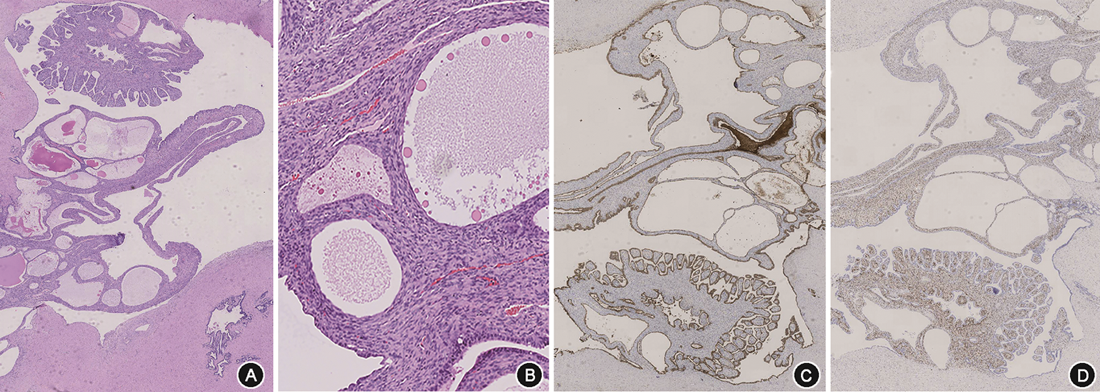

病理检查:大体观察示左精囊腺大小2.5 cm×1.0 cm×1.0 cm,切面呈囊实性,囊腔最大径约1.2 cm,实性区切面灰白质中;右精囊腺大小1.5 cm×1.5 cm×0.5 cm。前列腺大小4.8 cm×3.5 cm×3.5 cm,切面示左后上方呈多房囊性,囊腔最大径2.5 cm。镜下观察:肿瘤由多量大小不等的囊腔组成,呈圆形、卵圆形或不规则形,囊腔衬覆单层或多层立方上皮,局灶可见乳头状内折,细胞无明显异型;囊腔间为弥漫增生的短梭形细胞,细胞密度较高,总体较一致,局灶可见细胞多形性,未见明确核分裂象。免疫组织化学:上皮细胞PAX8、细胞角蛋白(CK)7阳性,间质细胞雌激素受体(ER)、孕激素受体(PR)阳性,CD34、平滑肌肌动蛋白(SMA)部分阳性,PSA、NKX3.1、癌胚抗原(CEA)、WT1阴性,Ki-67阳性指数1%~2%阳性(图2)。

病理诊断:精囊腺混合性上皮间质肿瘤,低级别,最大径3.7 cm,位于左精囊腺和前列腺左后上部。